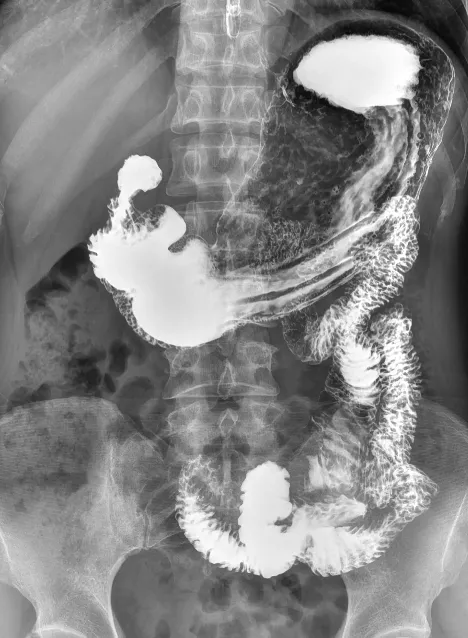

食道造影 消化道造影 灌肠造影 输卵管造影

动态DR属于多功能诊断专用设备,具备全身数字化摄片,数字化透视,数字化造影(如T管造影图),脊柱、四肢全长摄片(拼接图)及职业性尘肺体检等功能。可做消化道造影检查,作为数字胃肠机的较好备用补充。与传统DR设备不同,动态DR解决了传统DR盲拍的劣势,具有可视化操作功能,尽可能地避免误诊发生,极大地提高了诊断的准确性。动态DR已不再局限于简单的拍片功能,而是具有高的高清拍片、大幅面透视、高清点片、实时回放、自动曝光控制、全身拼接等多种功能。

从功能上来说,动态DR集常规拍片、胃肠、透视、造影于一体,可应用于临床各科室,如体检科、内科、外科、骨科、急诊科等,临床用途更加广泛。此外,动态DR具有大幅面(17×17英寸)高清拍片、大幅面透视、视频实时保存回放、可视化造影、毫秒级点片等基础功能,以及全景拼接等更多高级智能应用。在各类常规及特殊造影,如消化道造影、静脉肾盂造影、T管造影检查上有大量需求,在全身各部位摄影,包括常规摄影(如:胸片、颈椎、腰椎、腹部、头颅、四肢等)和特殊摄影(如:髌骨轴位、跟骨轴位、瓦氏位等)上有广泛检查需求,同时在开展全身拼接、特殊体检上有一定的业务需求。多功能动态DR融合数字化摄影、数字化造影、数字化透视、全身拼接、尘肺检查于一体,同时配备的精准诊断保障功能,如:视频保存回放、动静极速切换、局部放大观察等,完美满足了综合性医院的高标准综合需求。